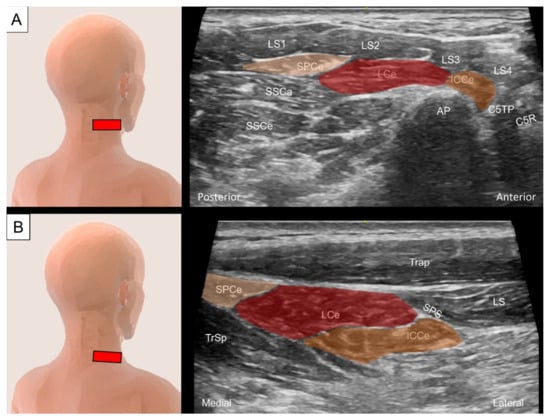

4.1.2. Sonographic Scanning

4.2.2. Sonographic Scanning

4.3.2. Sonographic Scanning